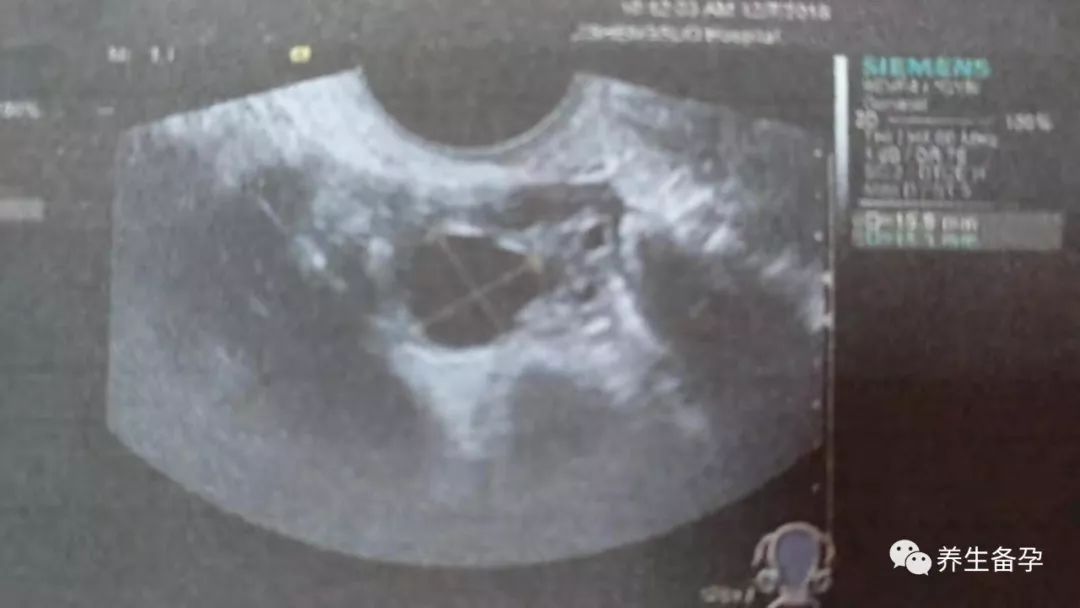

下面给大家看看卵泡质量比较好的照片。